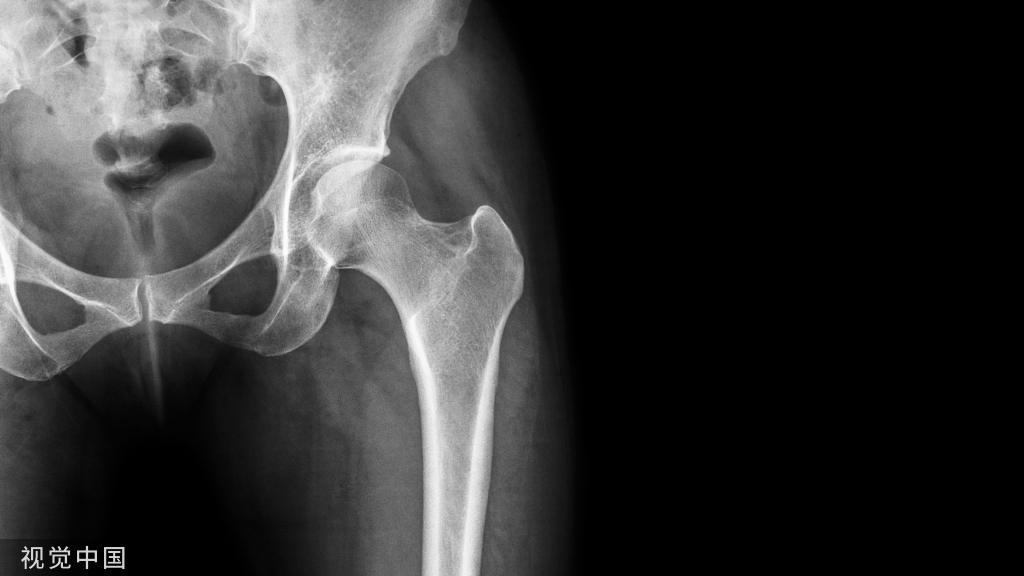

最新版指南:骨质疏松分级诊疗政策!

骨质疏松分级诊疗是对骨质疏松患者全程管理,早发现、早诊断、早治疗,全程管理的人群可分为4组:骨密度正常、骨量减少、骨质疏松、严重骨质疏松。对每组人群治疗制定相应的防治方案,畅通转诊,连续治疗。